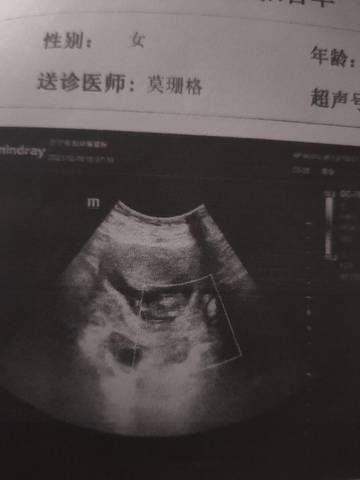

哪个才是孕囊,为啥给我复印一张,我彩超单收走了!怎么看孕囊形状

看不出来,你看一下在上面的说明就行了,文字上面宝宝的发育是有胎心,胎芽发育好就可以。